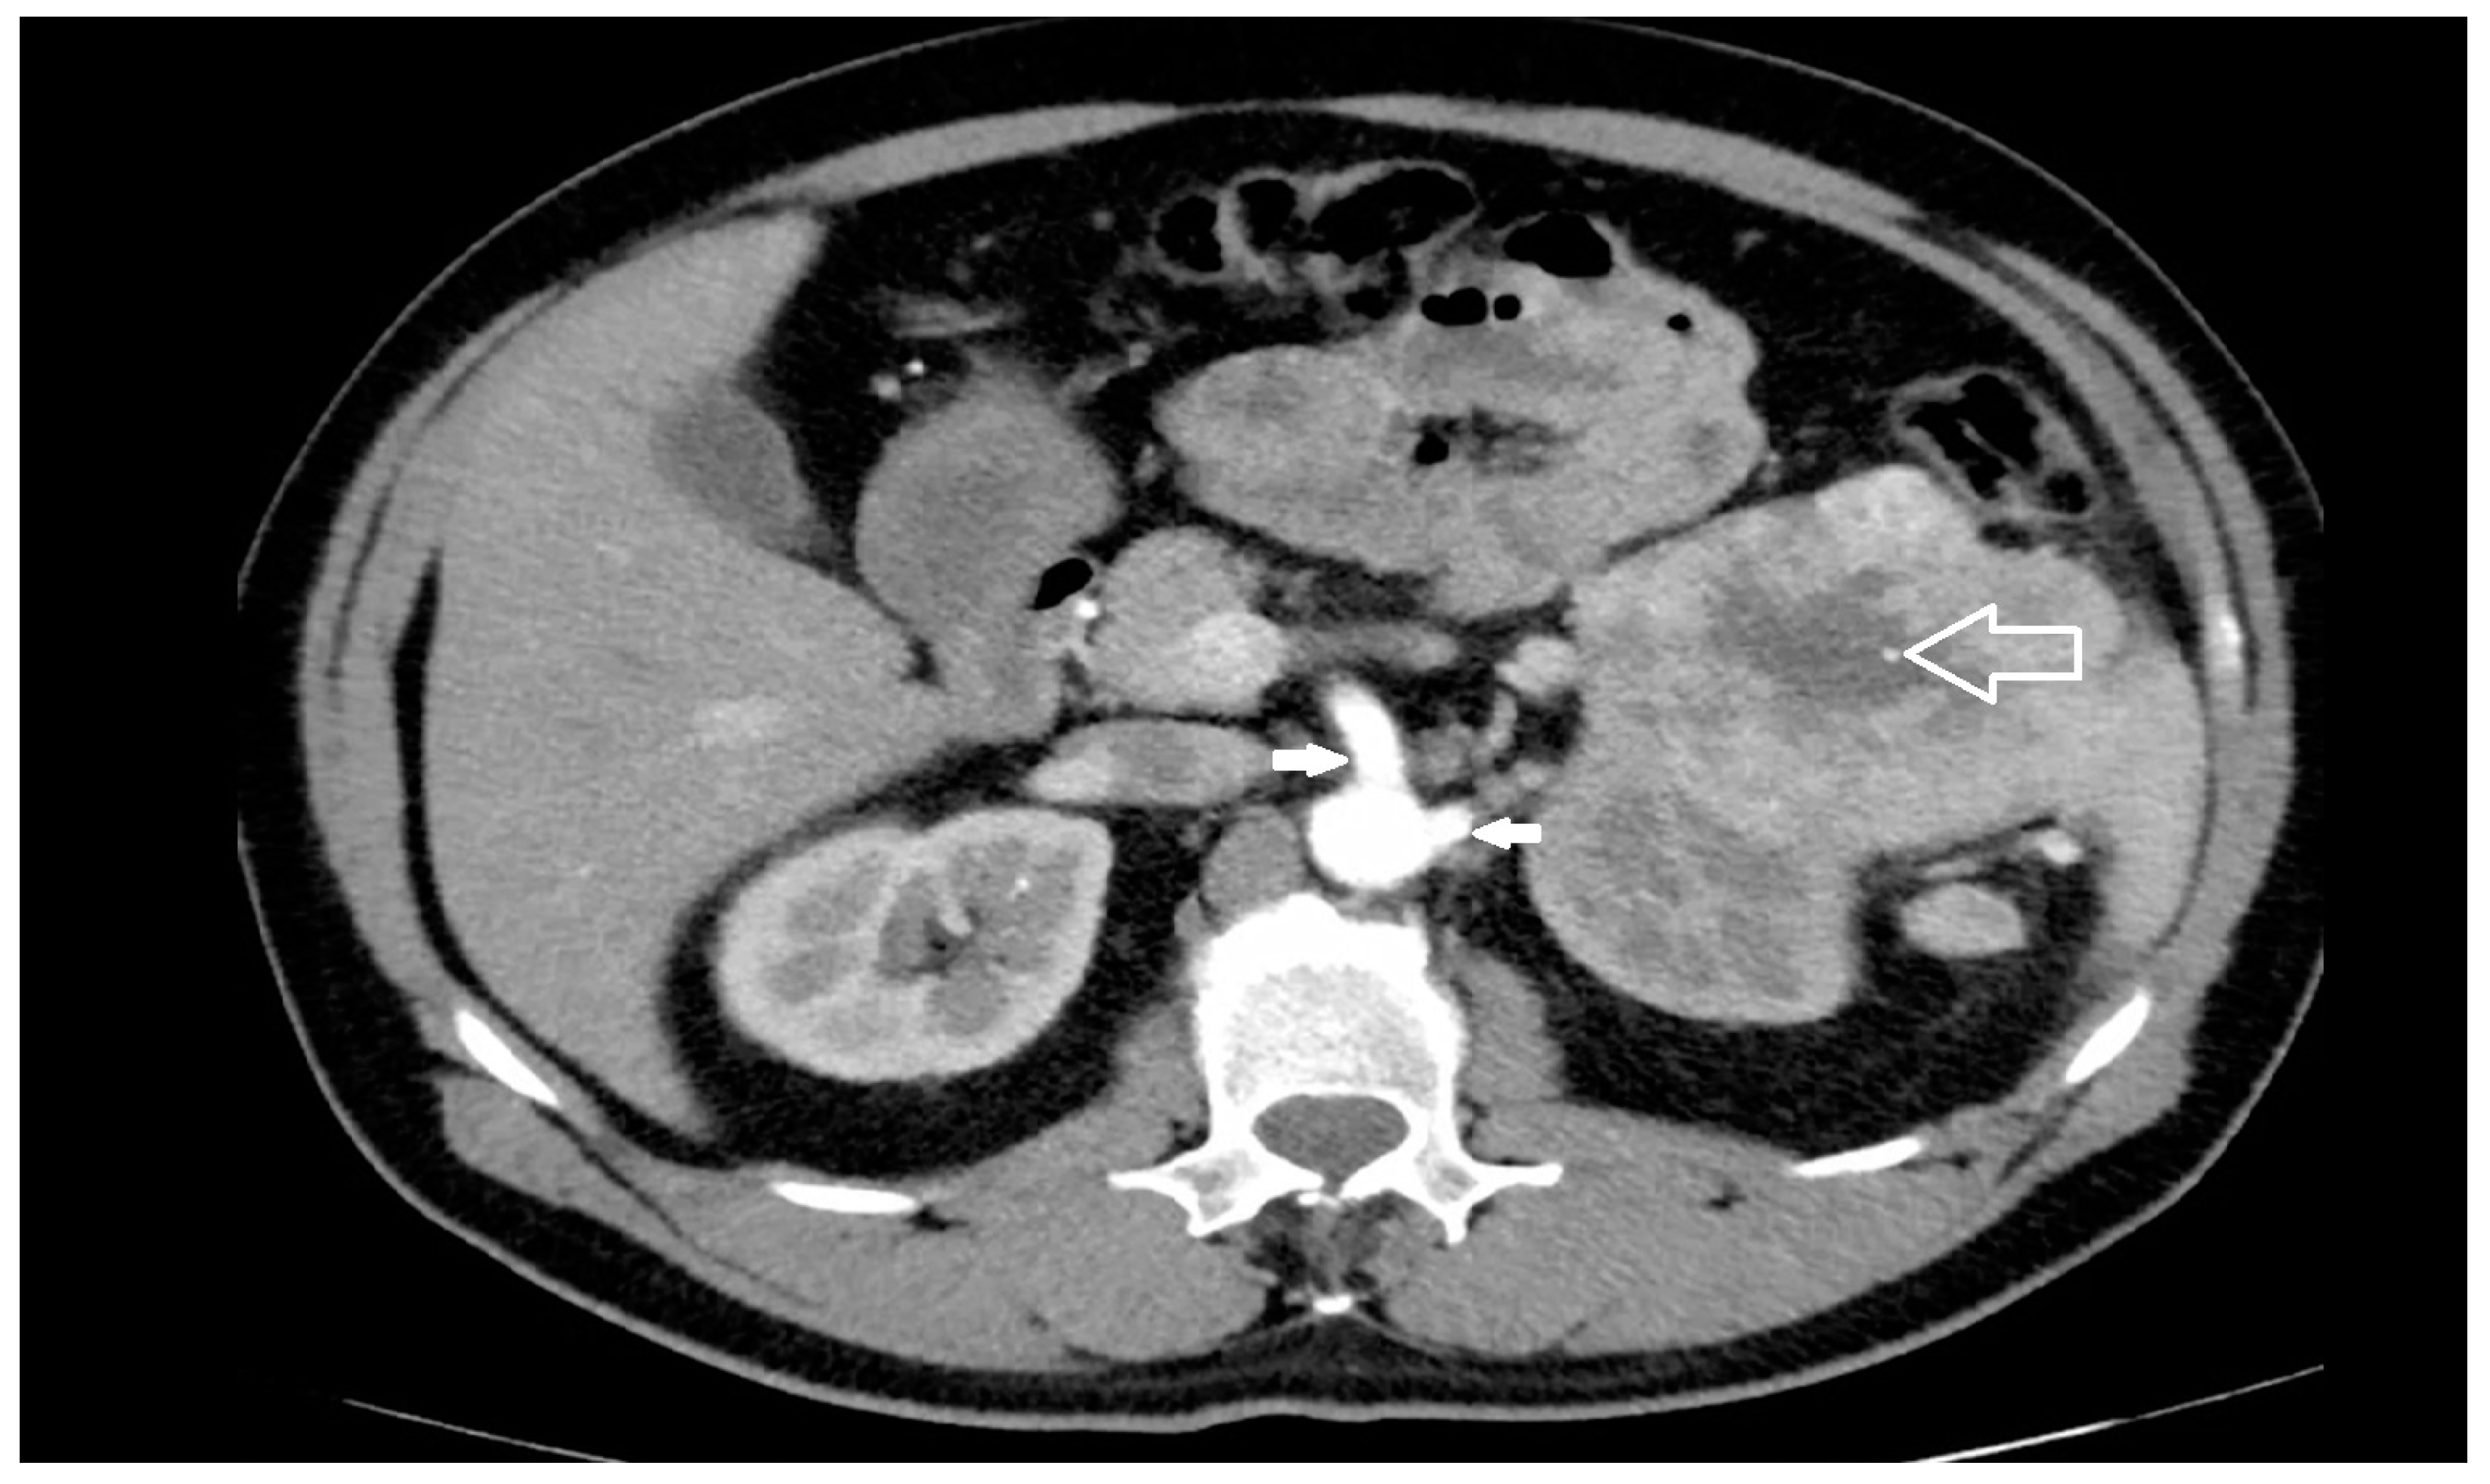

2.4. Spatial Relationships

3.2. Risk Factors

3.3. Pathogenesis, Prevention and Diagnosis